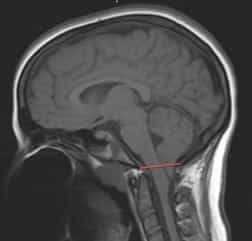

Рисунок 2.- МРТ пациента в 8 и 20 месяцев, на втором снимке можно наблюдать опущение миндалин мозжечка, которое появилось уже после первого МРТ. Huang P. “Adquired” Chiari I malformation. J. Neurosurg 1994. Это указывает на то, что, помимо наследственного и генетического фактора, существует фактор приобретенного заболевания.